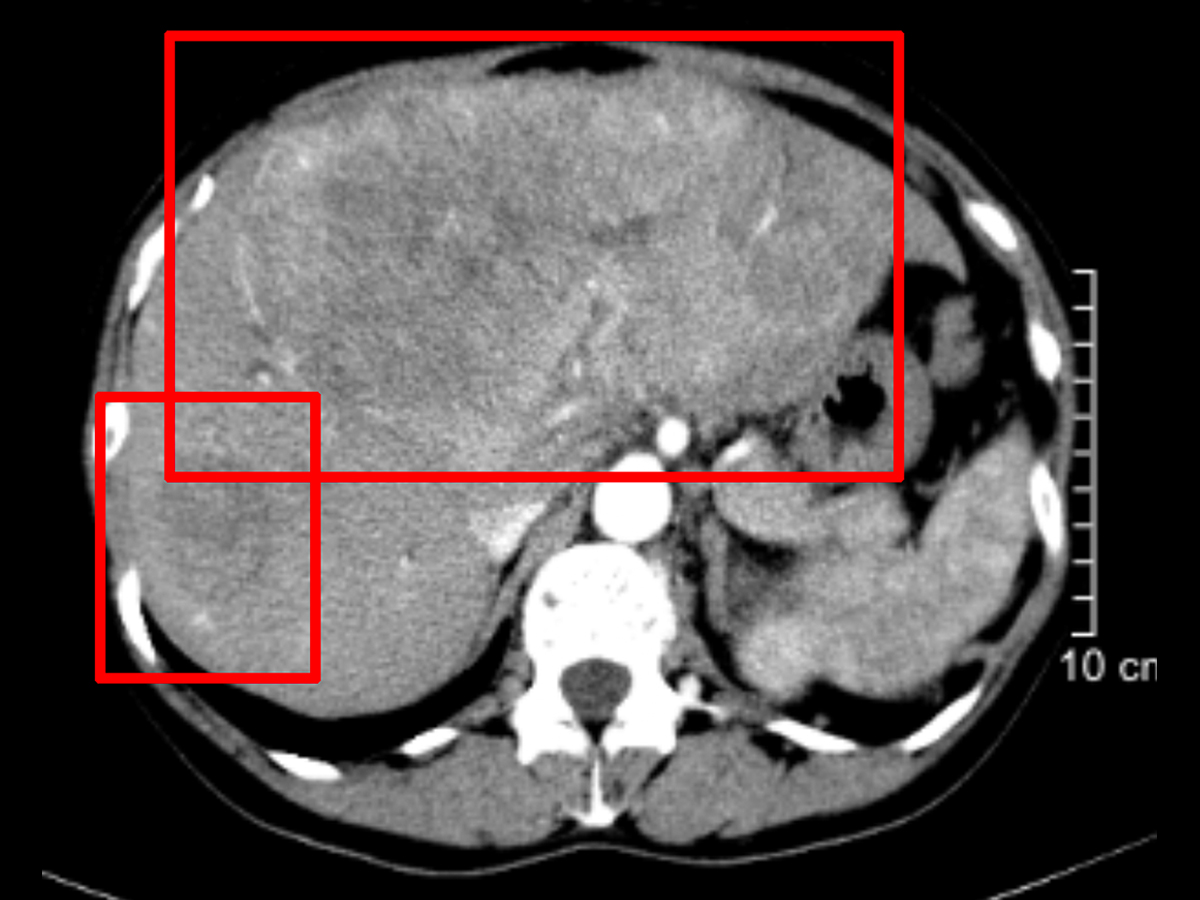

肝惡性腫瘤02.jpg

三、治療效果

雖然患者腫瘤巨大,血供來源豐富,但經(jīng)過5次的積極介入治療下,腫瘤的血供仍然獲得了比較理想的控制效果。而應(yīng)用甲磺酸侖伐替尼膠囊進(jìn)行靶向治療和應(yīng)用PD-1抑制劑納武利尤單抗注射液進(jìn)行的免疫治療,也對(duì)腫瘤取得了較好的控制效果,治療至今,暫未發(fā)現(xiàn)腫瘤出現(xiàn)轉(zhuǎn)移,在一定程度上給患者爭(zhēng)取到了治療時(shí)間,也延長(zhǎng)了患者的生存時(shí)間,這算得上治療過程中的第一步成功。該患者十分幸運(yùn),在如此晚期的情況下仍然獲得了較好的控制效果,如果后期腫瘤縮小到一定程度,還可再進(jìn)行手術(shù)切除,屆時(shí)將會(huì)獲得更好的治療效果。